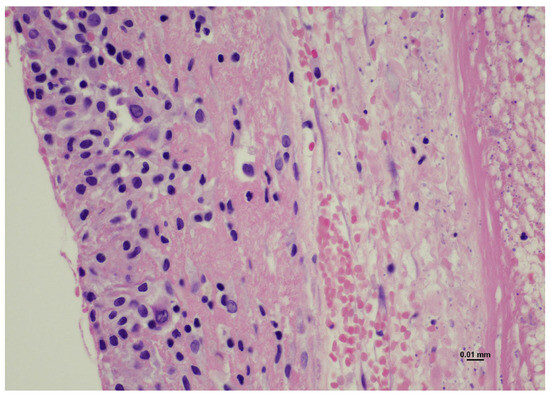

2.2. Histological Examination